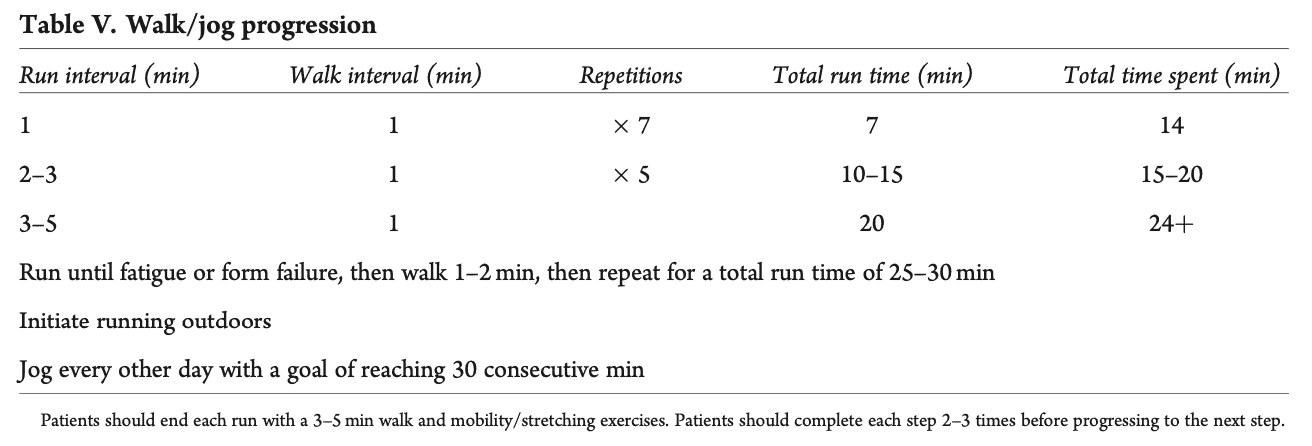

- Първата фаза на тази програма е програма за ходене, която започва на бягаща пътека и преминава към дейности на открито. Изискването беше да можете да вървите 30 минути със скорост около 3,5 мили в час, което съответства на 5,6 км/ч.

Преминаването към програмата за ходене/бягане е разрешено, когато участниците са завършили успешно фаза 1 и плиометричната програма от ниво I на фаза 2, могат да ходят без да куцат и нямат болка при ежедневните дейности. И тук съветът беше тази програма да се започне на бягаща пътека. Трябваше да се спазват следните правила: (i) без хълмове и наклони, (ii) без работа за скорост, (iii) работа върху формата и (iv) бягане всеки втори ден. В идеалния случай те трябва да продължат плиометричната програма от II и III ниво.